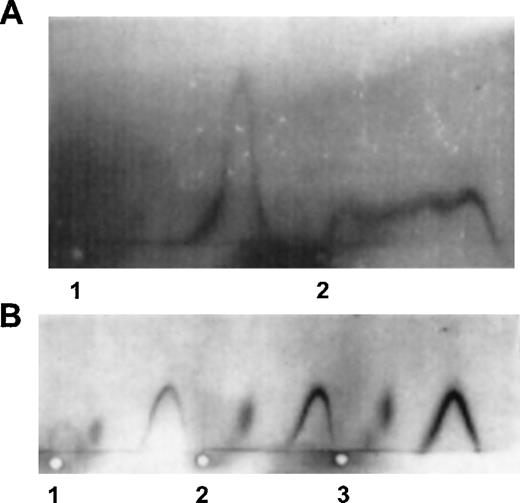

Direct evidence for the binding of the patient’s IgG to APC was obtained by crossed immunoelectrophoresis (Fig 2). Addition of patient’s IgG to purified APC yielded a shoulder in the precipitin line representing immune complexes between the two (Fig 2A). No such shoulder was observed with control IgG. When normal plasma was used as a source of native protein C, the patient’s IgG had no effect on the electrophoretic pattern (Fig 2B). Therefore, the patient’s IgG had an affinity only for the activated form of protein C. Notably, the patient’s antibodies against APC did not react with denatured APC transferred onto a membrane as examined by Western immunoblotting analysis (data not shown).

Crossed immunoelectrophoresis of purified APC (A) or protein C in plasma (B) in the presence of control or patient’s IgG. Polyclonal rabbit antihuman protein C antiserum was used for detection of either APC or protein C as described in Materials and Methods. (A) Electrophoresis of 20 μL TBS-BSA containing 150 ng APC and 200 μg of control IgG (1) or patient’s IgG (2). (B) Electrophoresis of 10 μL of patient’s plasma (1), a mixture of 10 μL of normal plasma (40 ng protein C), and 10 μL of normal IgG (140 μg) (2) or 10 μL of normal plasma and 10 μL (140 μg) patient’s IgG (3).